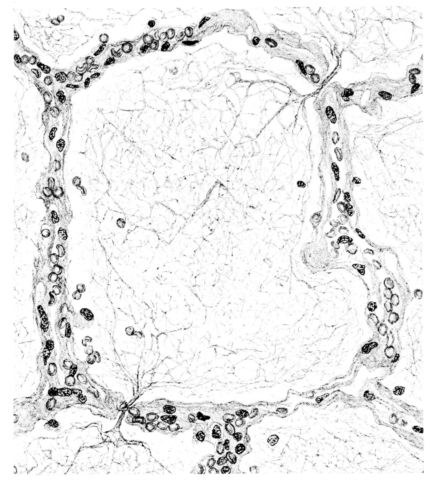

FIG. II. AUTOPSY NO. 98. DRAWING OF A SECTION THROUGH A TRACHEA SHOWING NECROTIZING HEMORRHAGIC INFLAMMATORY PROCESS OF THE MUCOSA.

The changes are less marked, perhaps, in the trachea than in its finer ramifications. The mucosa is constantly more or less destroyed and large areas, usually focal, are entirely devoid of their epithelial covering. This is replaced by a sparse exudate, composed largely of red blood cells, mucus, a small amount of fibrin, and nuclear fragments (Fig. II). It may dip into the submucosa for a short distance, but usually these indentures are associated with the ducts of the mucous glands into which the inflammatory reaction extends. A more striking feature than the exudate, however, is the edema and the congestion of the submucosa. The loose areolar tissue of the submucosa is spread widely apart, and throughout it distended blood vessels are very conspicuous. Occasionally such a vessel is broken and actual hemorrhage appears in the submucosa. Occasionally, too, the inflammation extends down the duct to the mucous gland itself, and here, also, aplastic inflammatory reaction is evident, inasmuch as the acini now stain intensely red with the cells undifferentiated from each other and specked here and there by broken remains of the dead nuclei (Fig. III). After the disease has continued for a short period, even at the end of five or six days, some regeneration of the epithelial lining may be seen (3) (Fig. IV). But despite this, the acute picture persists, and there goes on, side by side, an attempted repair characterized by epithelial regeneration and the same evidence of acute change. Since the lesion is essentially a superficial one, scars or contractures of any extent are not encountered in the trachea, even in examples of the disease that have ended fatally only after many weeks.[4]